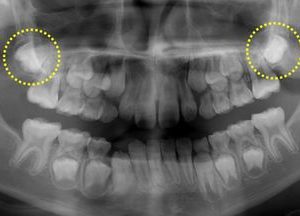

続きを読む丸印は、上顎の12歳臼歯の歯胚です。下顎の12歳臼歯の歯胚は本来矢印部分にあるはずですが、このレントゲン写真には写っていません。現状では、歯並び・咬み合せに大きな問題はないのですが、永久歯列(12歳~)になった段階で咬み ...